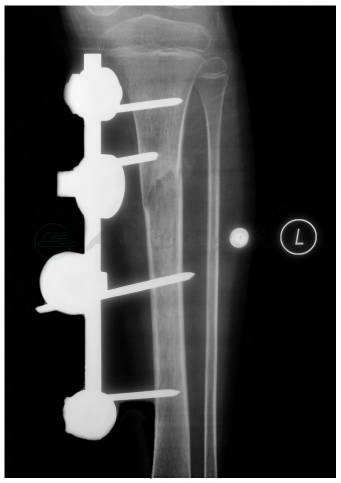

胫骨直接在骨折线两端各穿2枚3.0mm骨圆针,单平面外固定器固定。切口内置放引流管后关闭切口(图5)。

图4 左胫骨骨折骨外固定后X线片